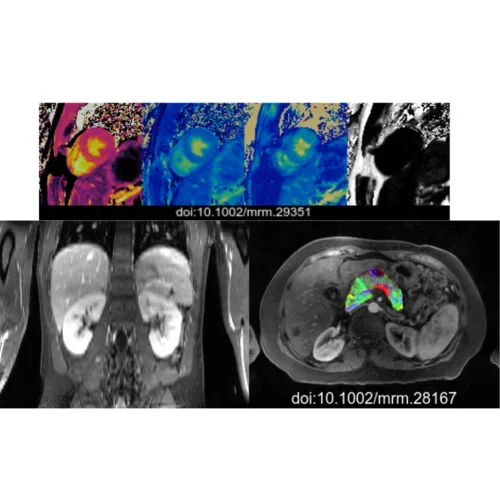

- MR physics, image reconstruction, and machine learning for cardiovascular diseases & cancer

- Motion-resolved quantitative imaging (e.g. free-breathing, non-ECG cardiovascular imaging)

- Multidimensional quantitative imaging and signal modeling

- Multi-dimensional qualitative and quantitative MRI techniques for cardiovascular and body applications